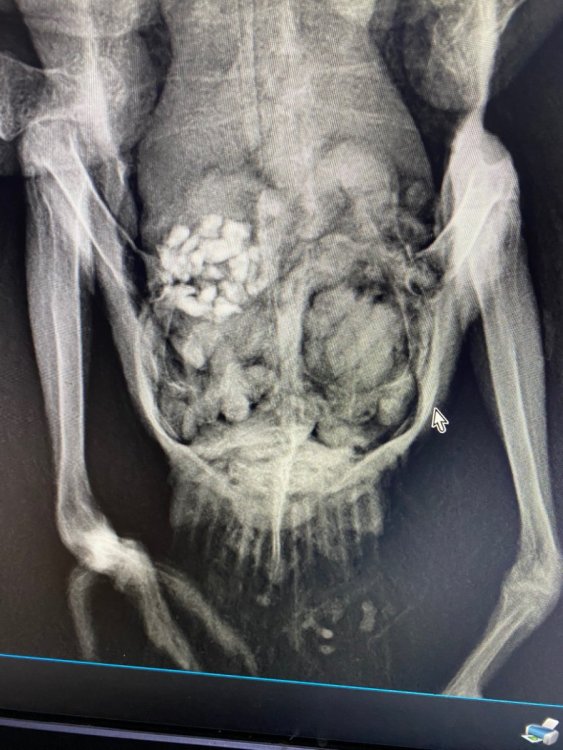

маленький принц Опубликовано 29 ноября, 2023 #126 Опубликовано 29 ноября, 2023 да у него пёрышки растут надо бы устроить купание налив в плошку чистой питьевой воды на сантиметр и затем поплескав в воде рукой чтобы он видел что там мелко и безопасно купание ОБЯЗАТЕЛЬНО под присмотром ВНИМАНИЕ сушить или греть феном птиц НЕЛЬЗЯ птицы очень легко травятся запахами горячего пластика потому что их лёгкие способны дышать разряжённым воздухом на огромной высоте В 17.10.2023 в 02:11, Анастасия Анатольевна сказал: а на лапках пока мы только так можем, попой кверху как сейчас ножки? В 29.09.2023 в 00:54, Анастасия Анатольевна сказал: @маленький принц здравствуйте! Извините пропала совсем( подходит к концу последняя неделя лечения Семен чувствует себя хорошо, на лапки не встаёт, сегодня сделали снимки ( он вырывался, поэтому держать пришлось вручную) сказали что все в норме с косточками и возможно это последствия на нервную систему какой-то инфекции и что ходить он не будет скорее всего 😭 удалось показать @Zosia рентген?